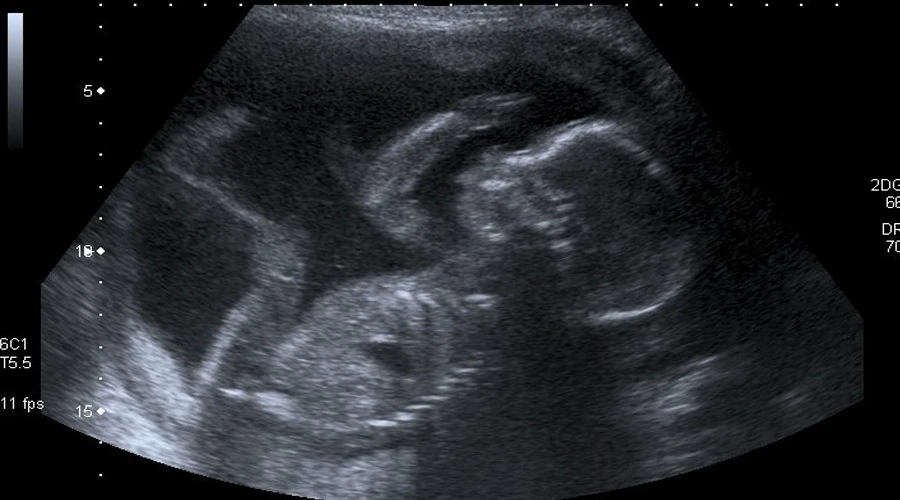

Entre las diversas intenciones que han recibido, May Feelings puso como ejemplo la de una mujer identificada como Elina, embarazada de 28 semanas a quien le han diagnosticado cáncer de cuello uterino. Ella quiere tener a su hijo pero los médicos le han dicho que aborte para salvar su vida. Esta madre pide a todos que recen por su intención.